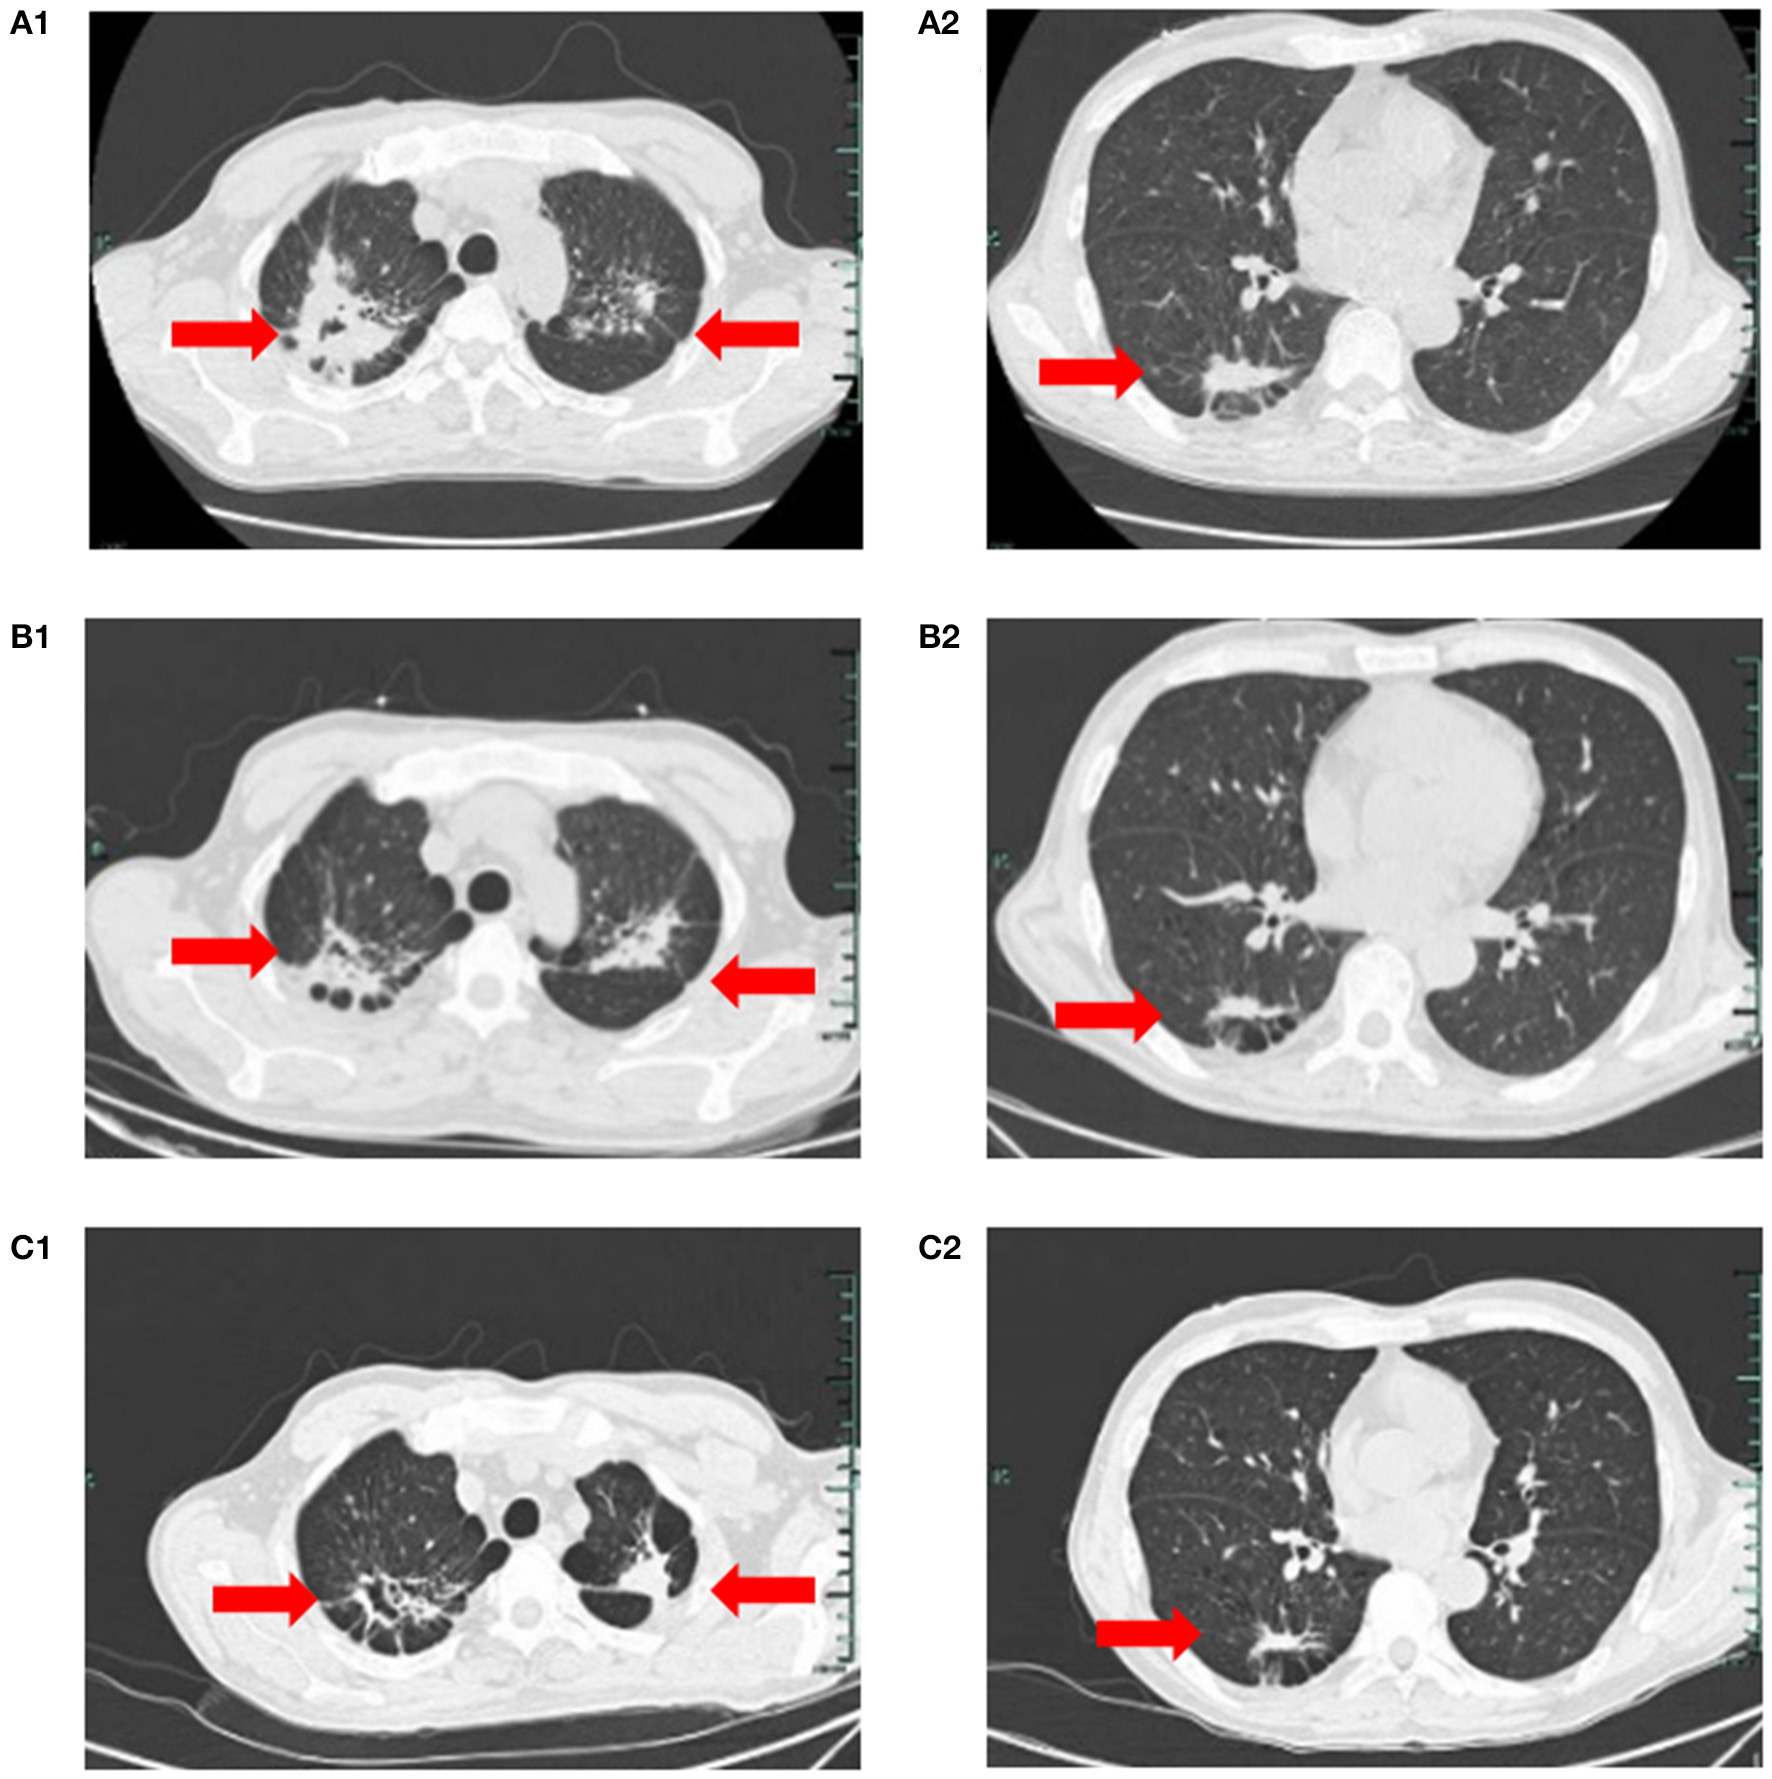

On March 23, the patient was transferred to the TB Department of our hospital. Blood counts were WBC 29.9 × 109/L, neutrophils 17.9 × 109/L, HB 60 g/L, PLT 175 × 109/L, with manual classification showing abnormal cells in 15%. Two pulmonary TB lesions were visible on a chest CT, and the right upper lung cavity had formed (Figures 1A1, A2). The patient immediately received HRZE (Isohydrazide 0.3 g QD + Rifampicin 0.45 g QD + Pyrazinamide 1.5 g QD + Ethambutol 0.75 g QD) regimen anti-TB therapy. The patient's WBC did, nevertheless, reach a maximum of 99 × 109/L, and neutrophils reached 59.8 × 109/L. He was treated with hydroxycarbamide for the purpose of reducing his WBC count. When sputum smears were negative for 3 consecutive times, blood counts were WBC 11.9 × 109/L, neutrophils 7.8 × 109/L, HB 52 g/L, and PLT 74 × 109/L.

Figure 1

(A1, A2) On March 23, chest CT suggested speckled and patchy high-density shadows can be seen in both lungs, with unclear boundary, and cavity shadow can be seen in the upper right focus; Right pleural cord adhesion. (B1, B2, C1, C2) on July 5, 2022, and on August 3, 2022, respectively reviews of chest CT suggested the lung TB foci progressive reduction.

On April 8, he was transferred to the Hematology Department of our hospital and started receiving VA (Venetoclax 100 mgd1, 200 mg d2–7+Azacytidine 100 mgd1–7) regimen anti-leukemia therapy immediately. Due to venetoclax and rifampicin conflict, the regimen of anti- TB regimen was adjusted to Levofloxacin 0.5 g QD + Isohydrazide 0.45 g QD + Pyrazinamide 1.5 g QD + Ethambutol 0.75 g QD. Following one course of the VA regimen, the bone marrow routine showed 4% primitive mononuclear cells and 35% naive mononuclear cells. A total 28% of juvenile mononuclear cells were identified by bone marrow flow cytometry. The chromosome was a normal karyotype. NGS highlighted DNMT3A (mutation rate 45.6%), FLT3-TKD (mutation rate 26.7%) and IDH2 (mutation rate 32.9%). On May 6, the patient was given HVA (Homoharringtonine 2 mg d1–7 + Venetoclax 100 mg d1, 200 mg d2–7 + Azacytidine 100 mg d1–7) regimen anti-leukemia therapy. On May 25, the blood counts routine showed WBC 5.2 × 109/L, neutrophils 4.7 × 109/L, HB 64 g/L, and PLT 336 × 109/L. The original mononuclear cells in the bone marrow routine were only 1%. Flow cytometry of bone marrow showed no blasts with obvious immunophenotypic abnormalities. NGS test exhibited DNMT3A (mutation rate 44.7%), and no mutation was detected in IDH2 and FLT3-TKD. After that, the patient underwent three cycles of the HVA regimen anti-leukemia therapy consecutively on June 1, July 8, and August 9, and no abnormalities were found in multiple bone marrow routines and flow cytometry. On August 23, NGS showed DNMT3A (mutation rate 46.5%), with no mutation detected in IDH2 and FLT3-TKD. Moreover, on July 5, and on August 3, respectively reviews of chest CT suggested the lung TB foci progressive reduction (Figures 1B1, B2, C1, C2). No AFB was repeatedly detected in the sputum. He was treated with intrathecal chemotherapy three times (cytarabine 50 mg + methotrexate 15 mg + dexamethasone 5 mg) for the purpose of preventing the growth of central leukemia. On September 15, the blood routine showed WBC 4.1 × 109/L, neutrophils 2.63 × 109/L, HB 121 g/L, and PLT 242 × 109/L. The patient has now had a bone marrow transplant. The adverse reactions of the patient during the use of HVA regimen are shown in Table 1.